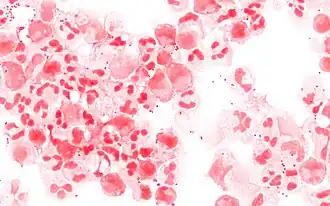

Coloration de Gram

Mélange de bactéries Gram + (S. aureus, violettes) et Gram – (E. coli, roses) visualisées en MO après coloration de Gram.